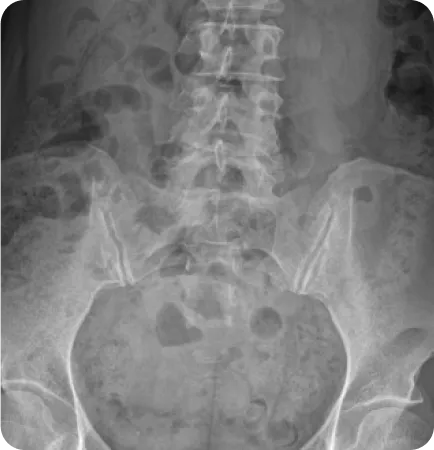

골반도 수학공식처럼 틀어지는 패턴이 있습니다.

Pattern 01.

회전성 부정렬

골반이 앞뒤로 회전한 상태 (80~85%)

Pattern 02.

골반 플레어 좁아진 골반과 벌어진 골반

골반 앞쪽이 벌어지거나 모인 상태 (40~50%)

Pattern 03.

업 슬립 골반 높이 차이

한 쪽 골반이 위로 올라간 상태 (15~20%)